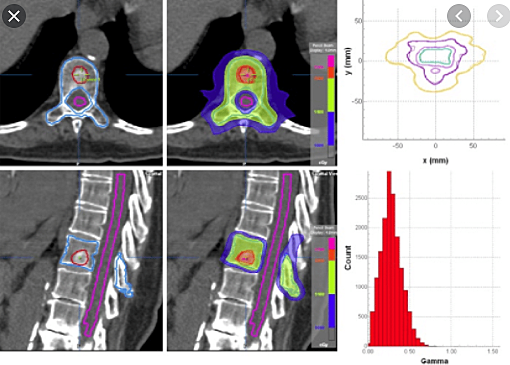

Starting of IMRT

Intensity-modulated radiation therapy (IMRT) is an advanced type of radiation therapy used to treat cancer and noncancerous tumors. IMRT uses advanced technology to manipulate photon and proton beams of radiation to conform to the shape of a tumor.